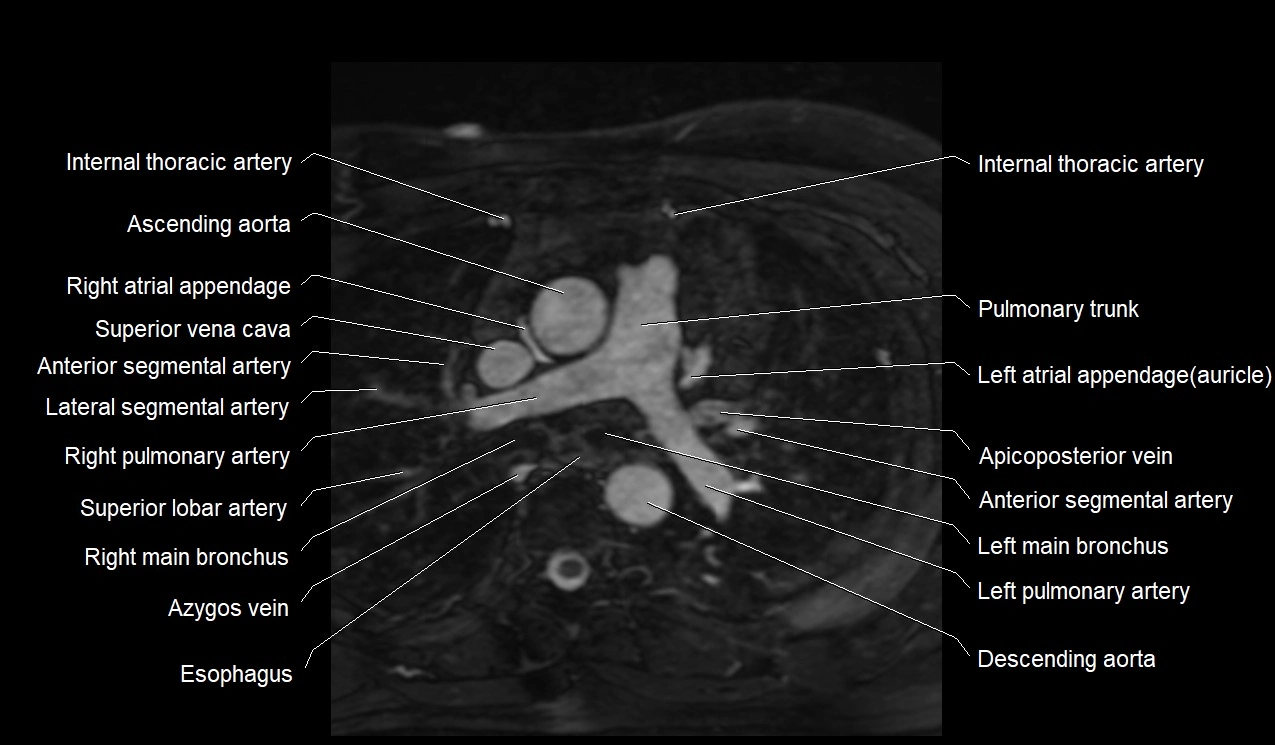

MRI image